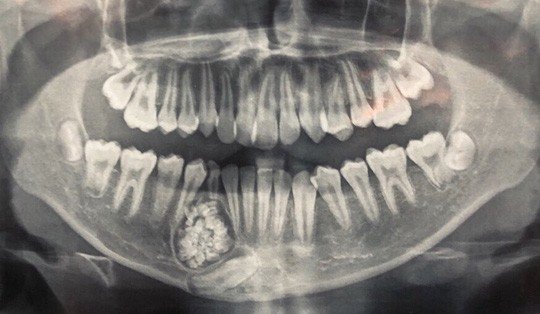

Hi hữu: Lấy gần 100 cái răng trong miệng một thiếu niên ở Khánh Hòa

Bệnh viện Đa khoa tỉnh Khánh Hòa cho biết vừa thực hiện ca phẫu thuật hi hữu lấy gần 100 cái răng của một bệnh nhân